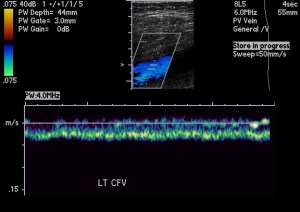

Doppler color ultrasound of the left common femoral vein with waveform.